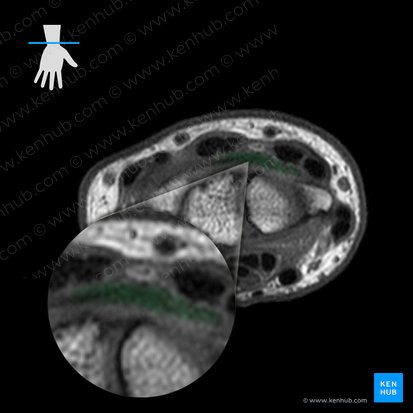

Ligaments

In contrast to the previous MRI image, there are several ligaments apparent in this axial view. You can see two thick, grey structures (intermediate intensity) spanning the superior and inferior margins of the radius, scaphoid and lunate bones. These are two extrinsic ligaments of the radiocarpal joint that connect the radius to each carpal bone; the dorsal and palmar radiocarpal ligaments. As their names imply, the dorsal radiocarpal ligament is located superiorly on the dorsal aspect. Its palmar counterpart is found inferiorly on the palmar aspect. Between the scaphoid and lunate bones you can see a thick, grey, interconnecting band. This is an intrinsic ligament of the radiocarpal joint which interconnects adjacent carpal bones. It is called the scapholunate interosseous ligament.

Continuing towards the left side (ulnar aspect), you can see two more grey thickenings overlying the lunate and triquetrum. These represent two extrinsic ligaments that connect the ulna to each carpal bone; the dorsal and palmar ulnocarpal ligaments. The former is located superiorly while the latter is inferior. It’s important to note that the radiocarpal and ulnocarpal ligaments are composed of several smaller ligaments, each named according to the carpal bone it connects to. However, they cannot be distinguished on this axial image. Last but not least, you can see the ulnar collateral ligament of the wrist joint on the far, extreme left. It connects the ulna to the triquetrum, so you can locate it very easily.